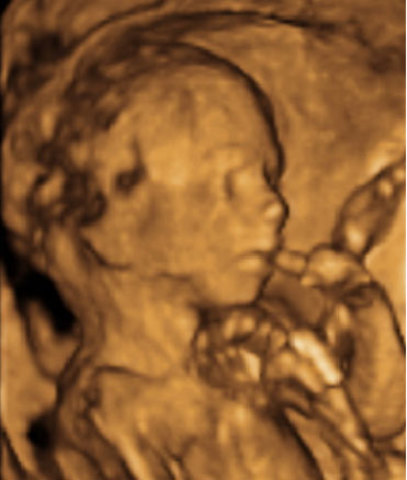

A las 11 semanas de embarazo el bebé pesa aproximadamente 8 gramos y pesará entre 4 y 6 centímetros. Vamos a poder ver grandes cambios a partir de ahora. Sus dedos están ya separados, las membranas que los unían han desaparecido. Aunque su cabeza sigue siendo la mitad de su cuerpo es completamente normal en este momento. Las orejas van migrando a su posición definitiva y el pequeño ya puede abrir y cerrar sus manos.

• Semana 12